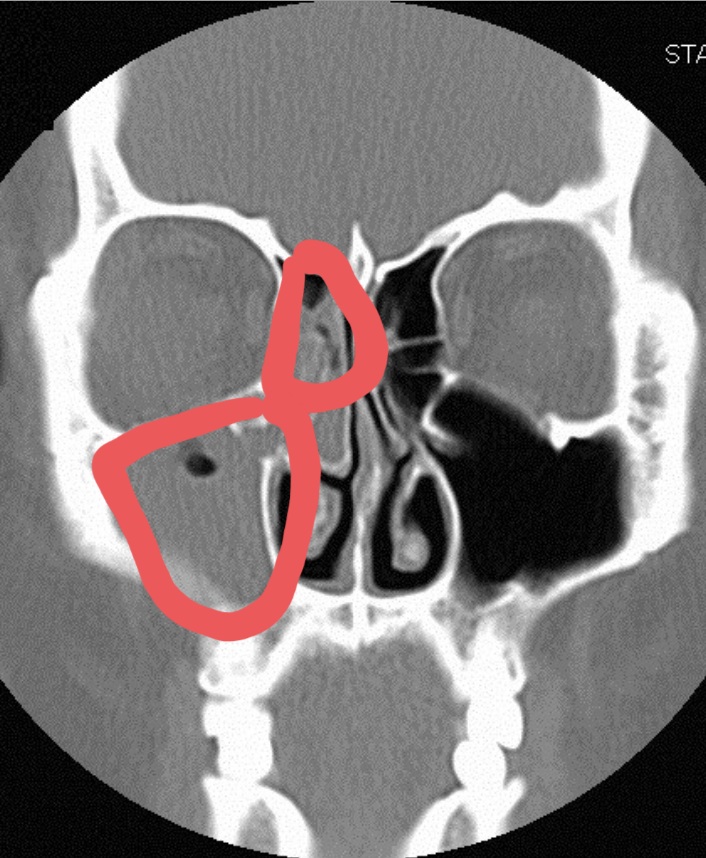

제 엑스레이는 아니지만 가능한 한 비슷한 사진을 보면 위의 사진처럼 붉은 부분이 반대쪽처럼 검게 비어 있어야 하는데 사진처럼 곪아 있더군요.

콧물이 순환하는 입구의 점막이 부어 있고, 양쪽이 딱 붙어 있었습니다. ;;;

그래서인지 그 부위를 만질 때 통증도 같이 있었는데 저같은 경우에는 오른쪽 그림의 빨간색으로 체크했듯이 미간과 눈 앞 꼬리에서 눈 밑까지 누르면 상당히 아픈 통증이 있었습니다.광대뼈 아래 뺨의 부부가 누르지 않아도 뻣뻣해지는 느낌이 들었고 #관자놀이의 통증과 치통이 심했어요.